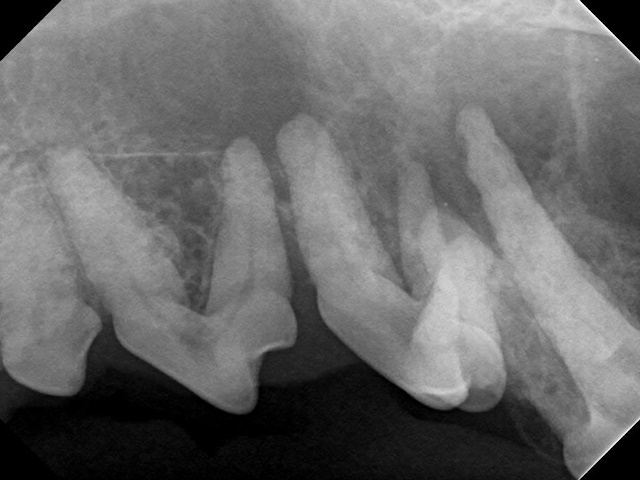

Intraoral radiograph shows significant bone damage around the roots of the premolars.